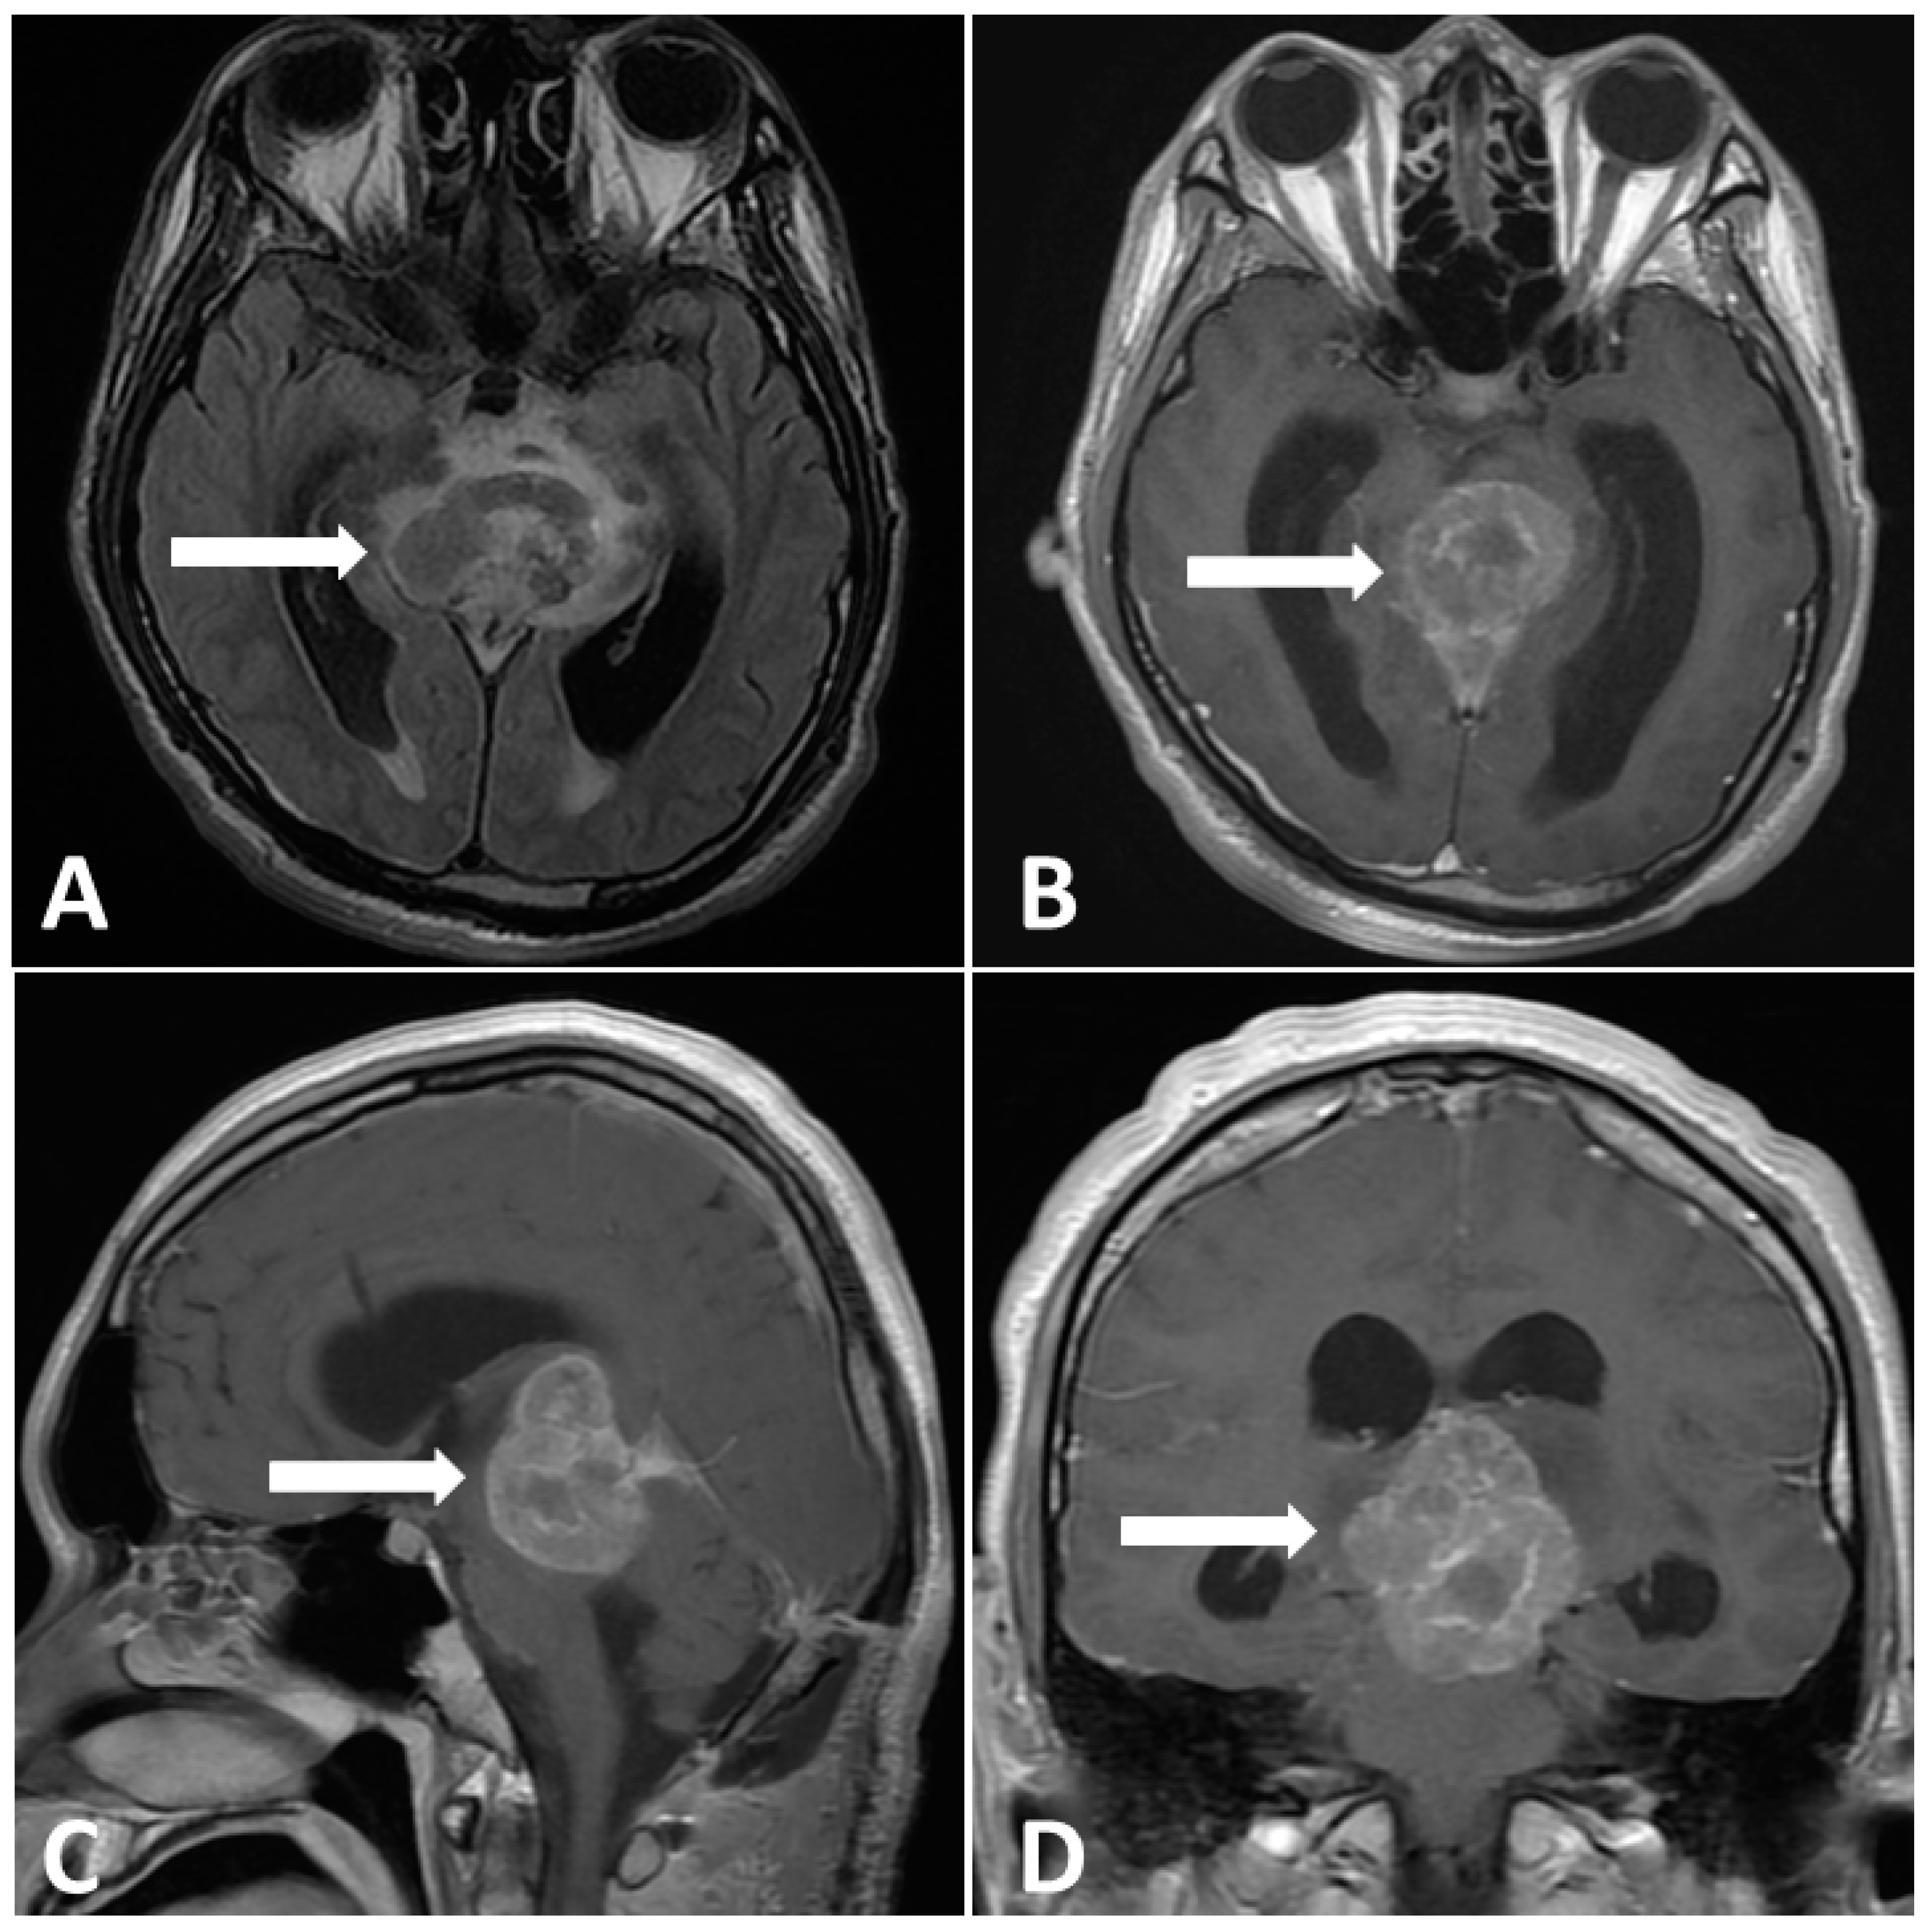

Figure 4.

Postoperative MRI performed 2 weeks after surgery. (A) Enlargement pineal tumor with perifocal edema on T2-FLAIR images. (B–D) Gadolinium-enhanced MRI, revealing a large pineal region tumor with heterogenous contrast enhancement.